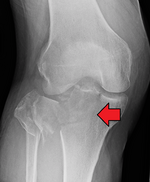

Segond fracture Paul Segond lateral tibial plateau avulsion fracture with anterior cruciate ligament tear Segond fracture at Who Named It? SegondFracture.JPG